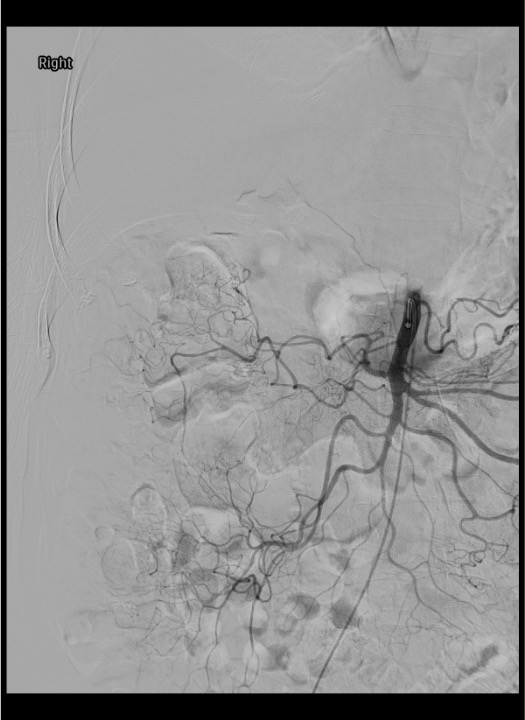

Selective SMA Angiogram